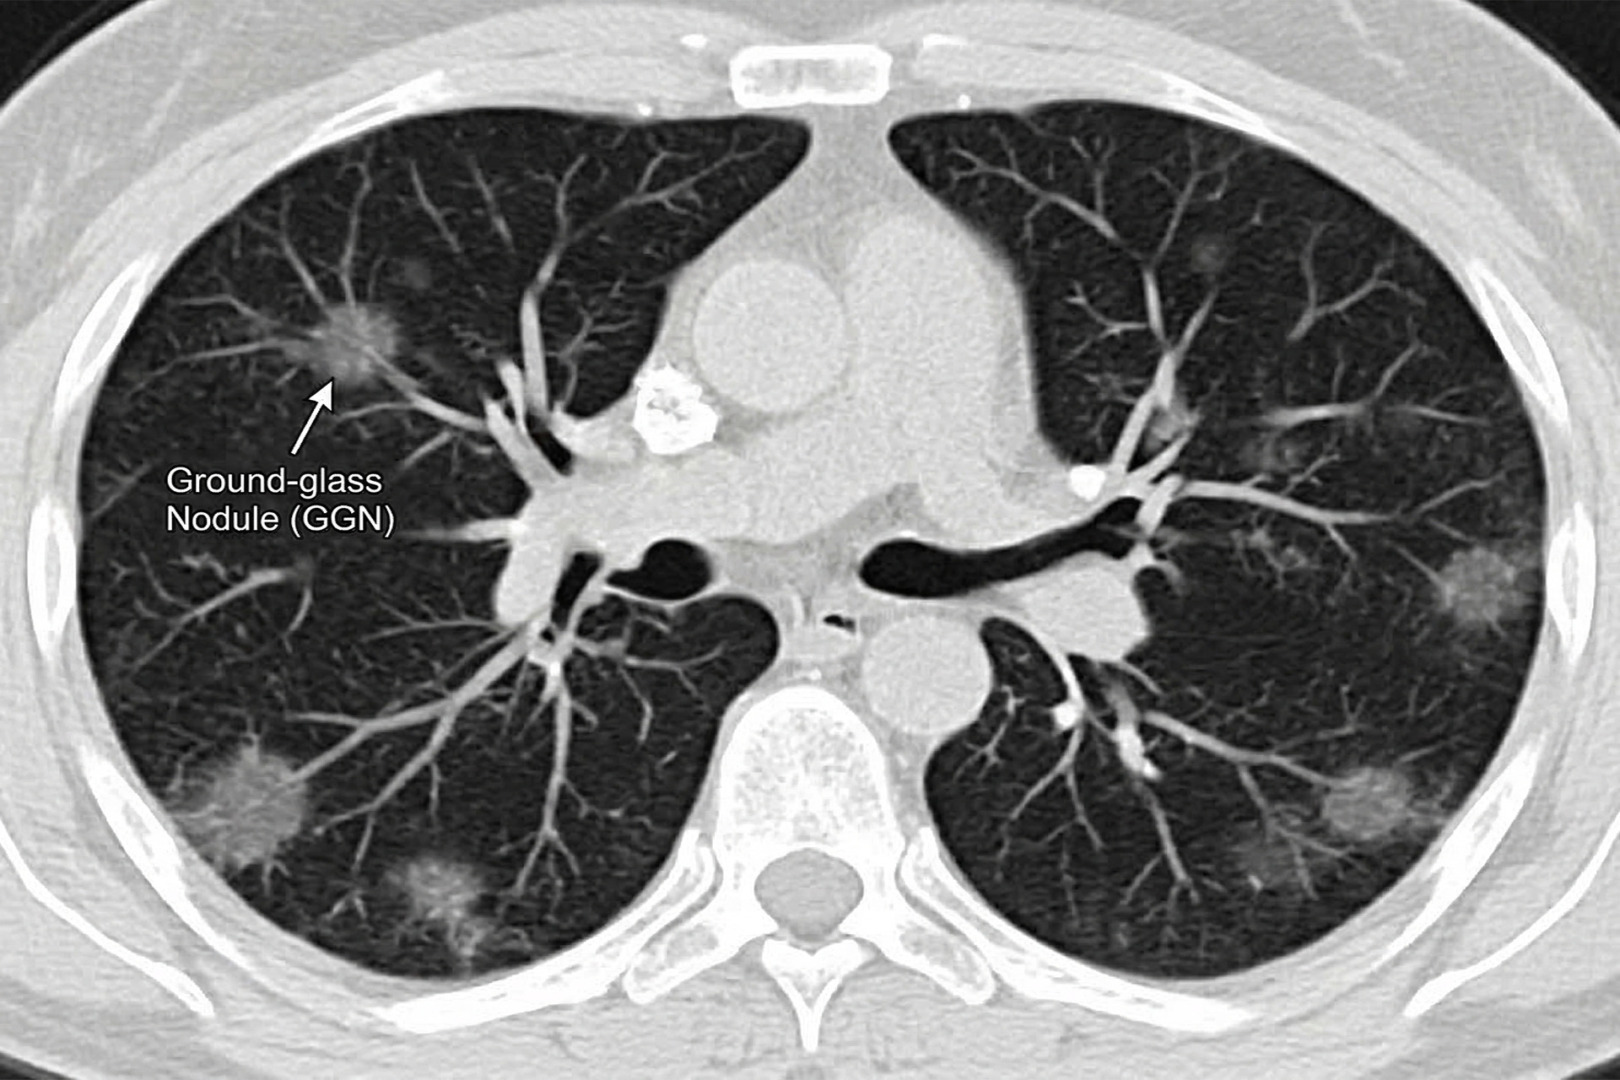

A ground-glass nodule (GGN), sometimes called a ‘ground-glass opacity’, is a faint, hazy area on a CT scan of the lungs that still allows normal lung markings to be seen through it. It is important to note that this is a description of how the nodule appears on imaging, not a diagnosis in itself.

- Pure ground-glass nodules (ground-glass opacity, nonsolid nodules) are entirely hazy and do not obscure underlying bronchial structures.

This distinction matters because part-solid nodules with solid components are more likely to represent early-stage lung cancer or lung adenocarcinoma than a pure ground-glass nodule of the same size. In the lung adenocarcinoma spectrum, ground-glass opacity may represent atypical adenomatous hyperplasia, minimally invasive adenocarcinoma, or invasive adenocarcinoma.